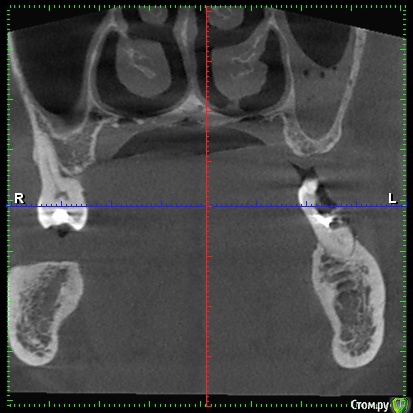

DenisV Опубликовано 11 декабря, 2017 Поделиться Опубликовано 11 декабря, 2017 Доктора, пациент обратился с целью установки имплантатов. На клКТ обнаружено затенение пазухи, отправлен к ЛОР на консультацию. Что это? синусит? ретенционка? Ссылка на комментарий

Большой Зеленый Опубликовано 12 декабря, 2017 Поделиться Опубликовано 12 декабря, 2017 Гайморит . 5 Ссылка на комментарий

Paganini Опубликовано 12 декабря, 2017 Поделиться Опубликовано 12 декабря, 2017 (изменено) Это синусит. И жалоб нет? Изменено 12 декабря, 2017 пользователем Paganini Ссылка на комментарий

колесников Опубликовано 12 декабря, 2017 Поделиться Опубликовано 12 декабря, 2017 Пузырьки газа в жидкости. Ссылка на комментарий